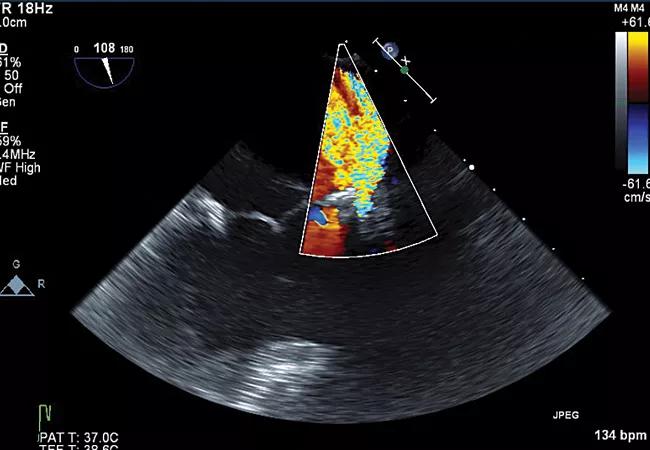

echocardiogram showing severe aortic regurgitation

Early Referral for Enlarged Roots Critical to Prevent Residual AR After Aortic Root Replacement With Valve Reimplantation

Residual AR related to severe preoperative AR increases risk of progression, need for reoperation